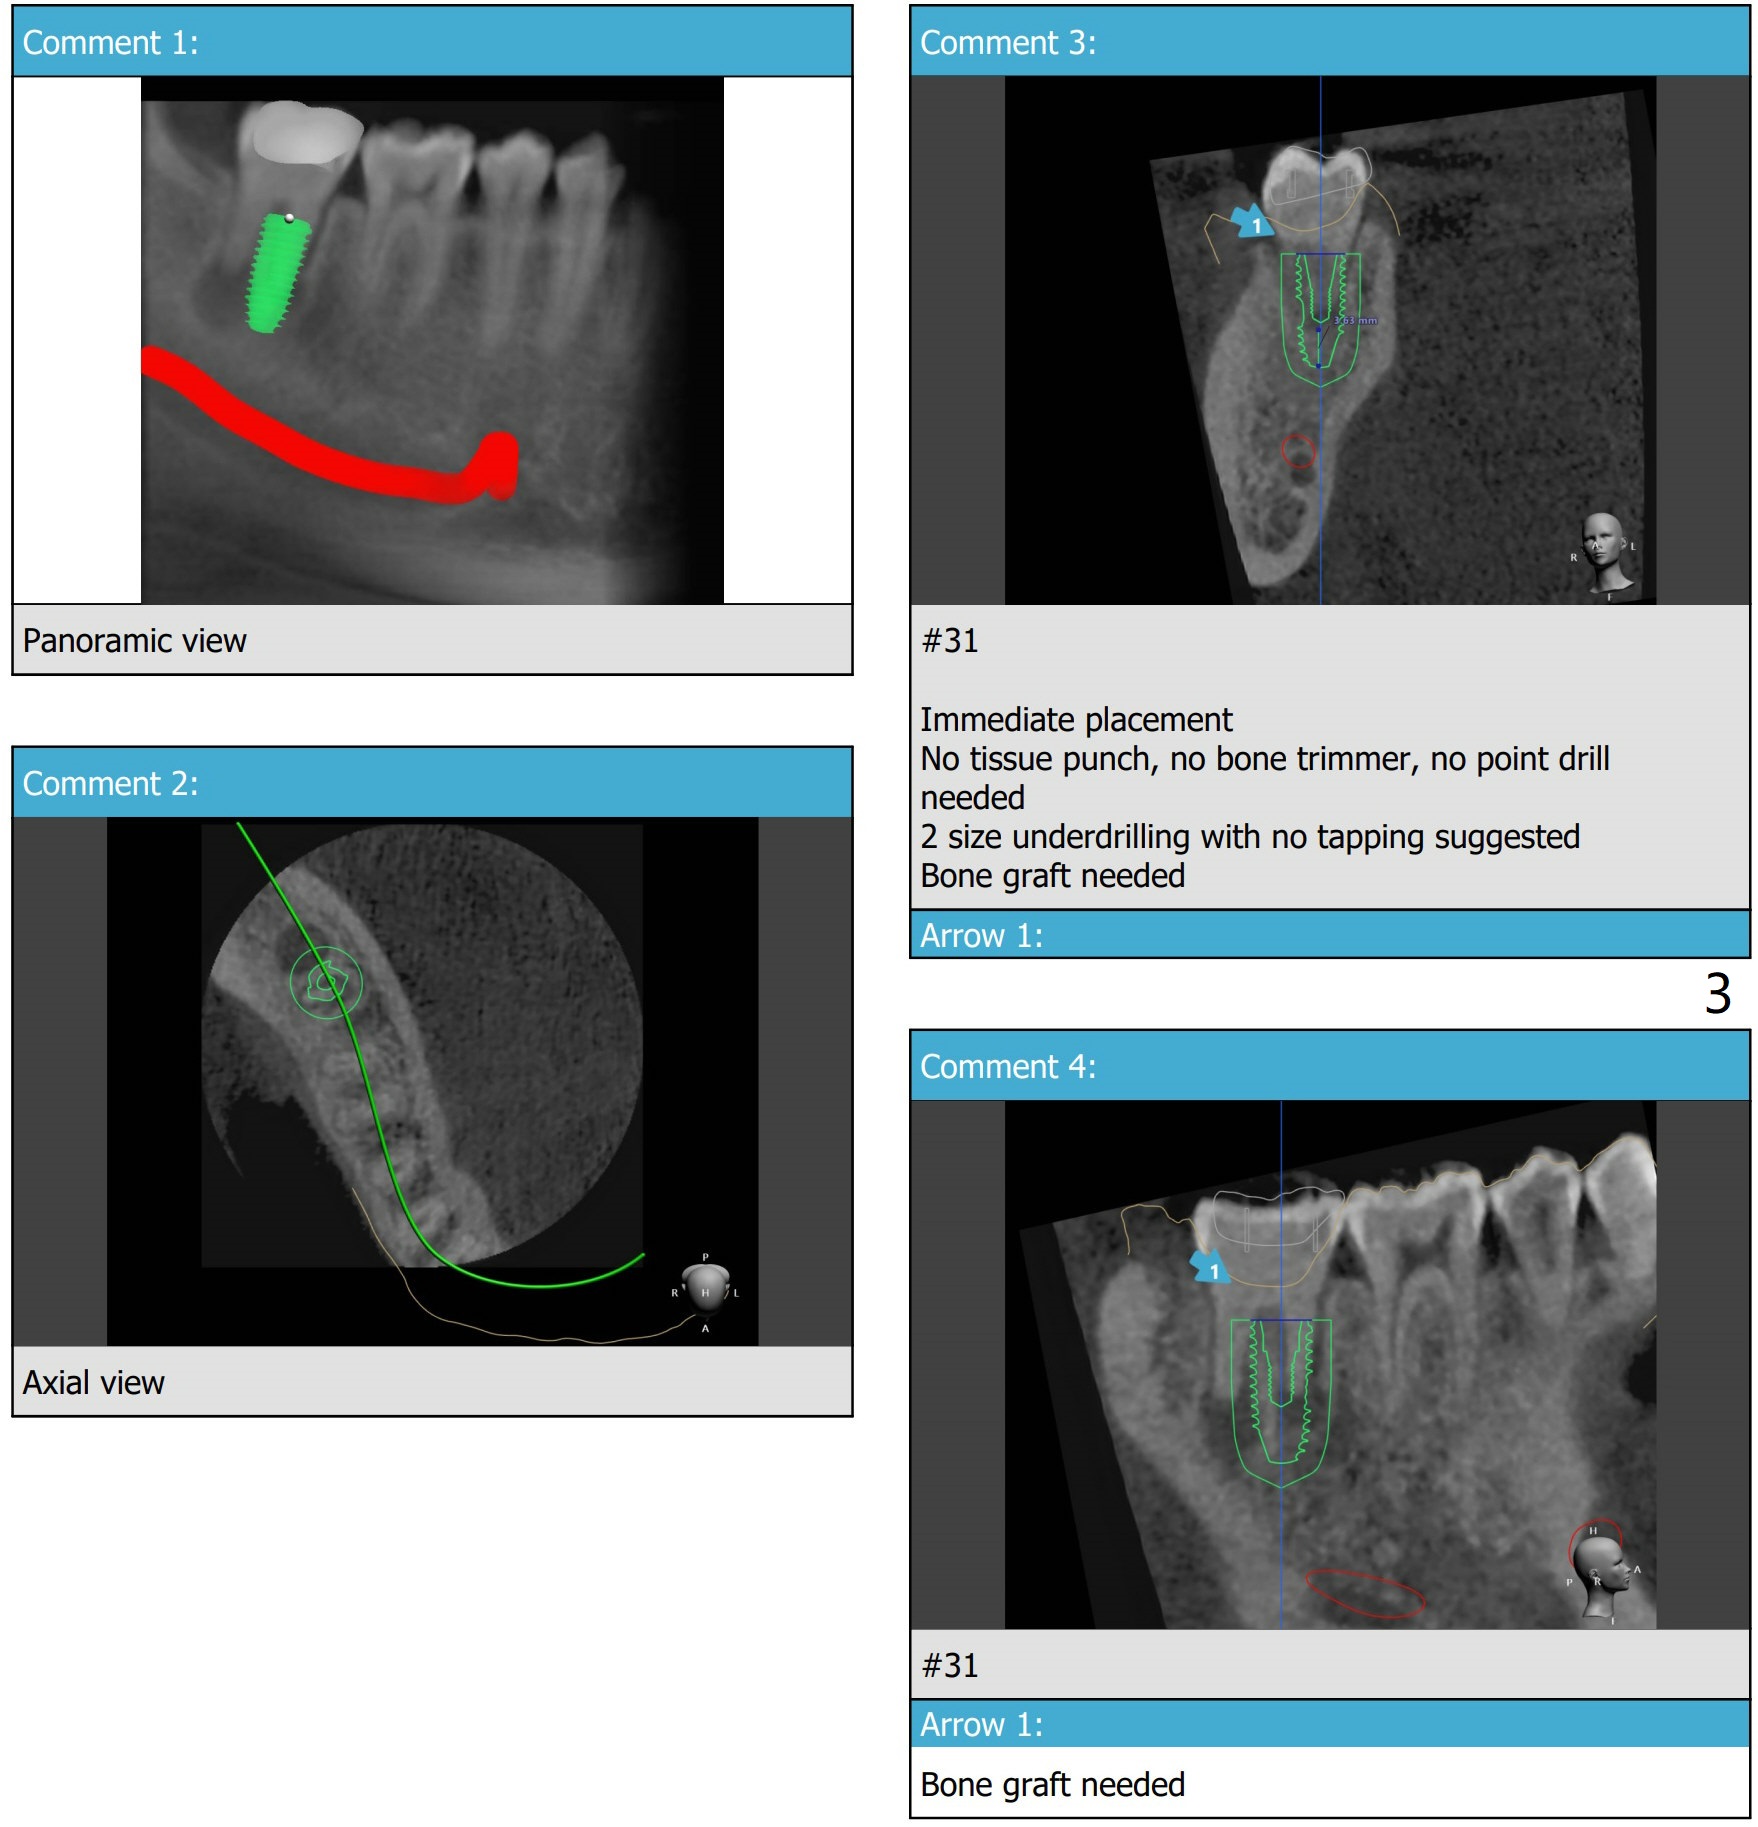

11.5 mm Implant for Lower 2nd Molar

A 30-year-old man wants #31 extracted for implant after the same treatment finished for #18.